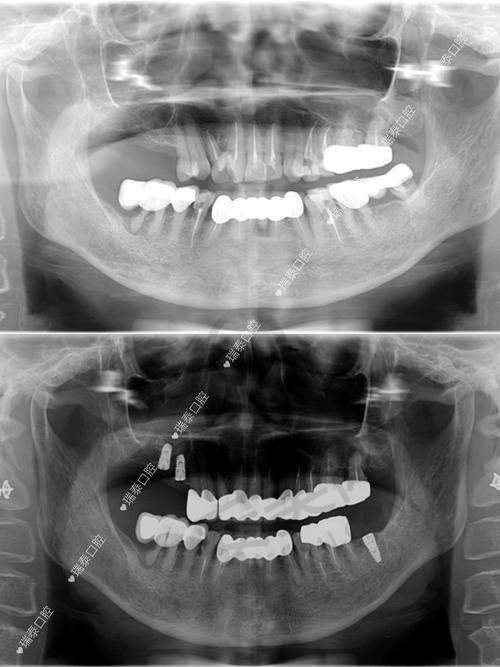

末尾是全口数字化种植设计。他利用CT、3D扫描等精良的技术手段,对患者的口腔进行全方面的检查和分析,然后严谨地规划种植体的植入位置和方向。这种数字化的种植设计不仅能够提高手术的正确性和安心性,还能减少手术创伤,缩短手术时间,让患者在更舒适的状态下完成种植牙手术。